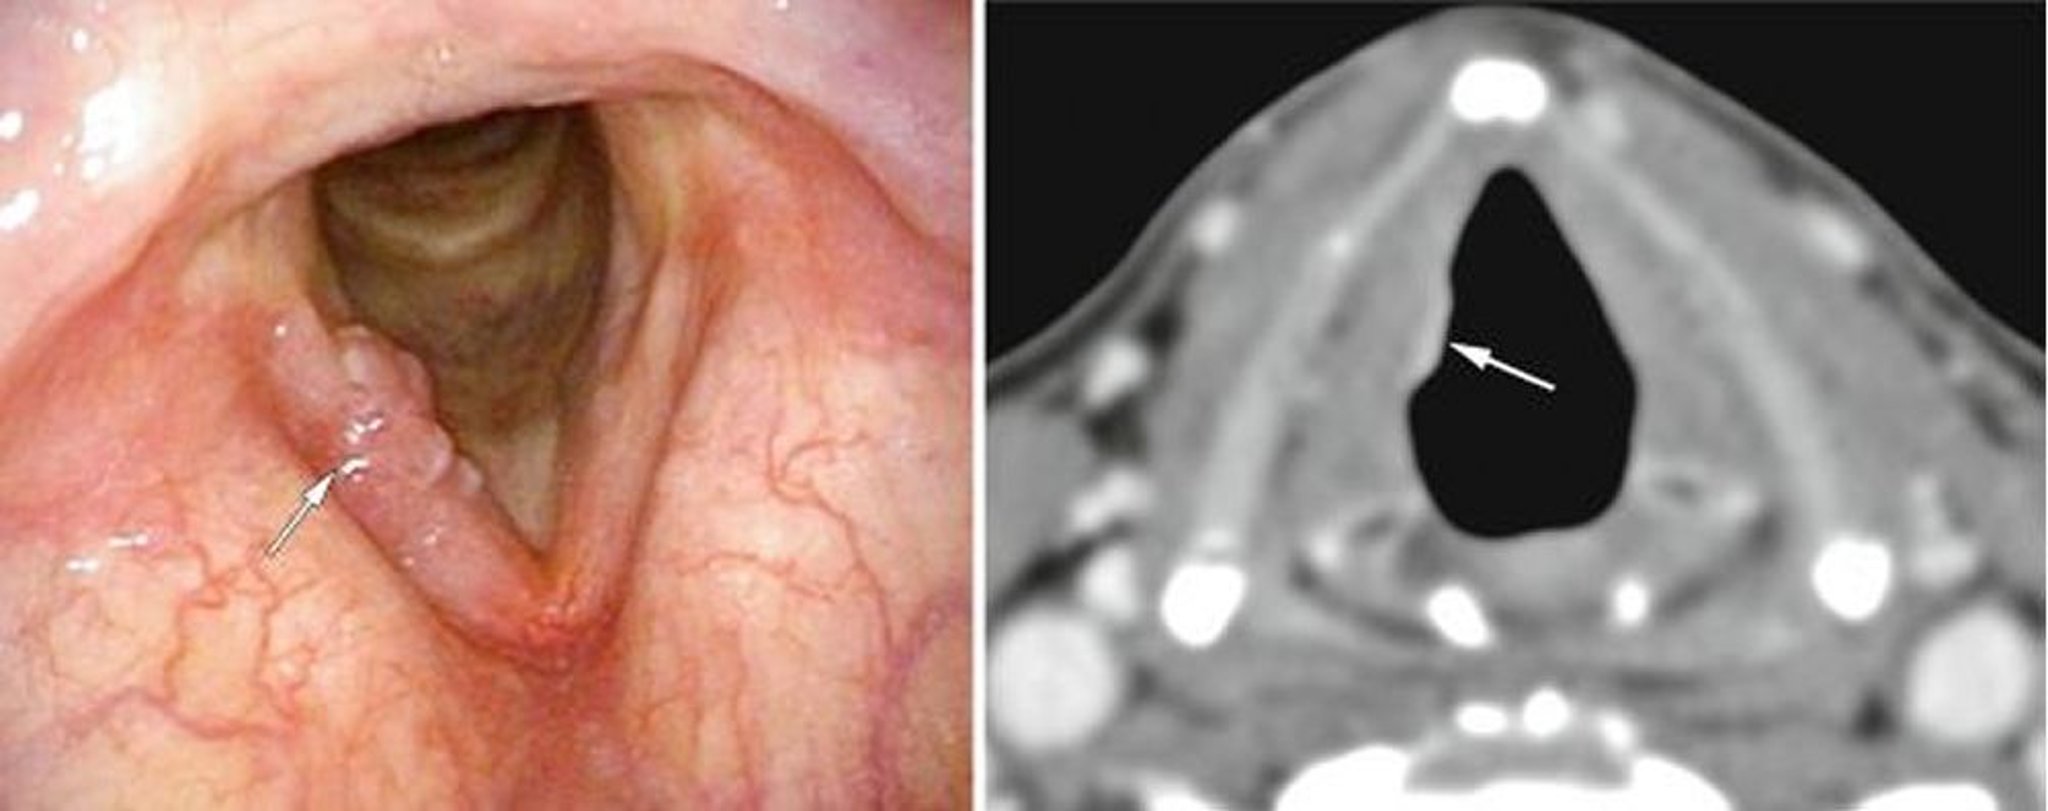

早期喉頭癌

この患者は早期声門喉頭癌を有しており,ここでは内視鏡像で一方の声帯に突出物として認められ(左の画像,白矢印),CT像で軟部組織の密度異常として認められる(右の画像,白矢印)。